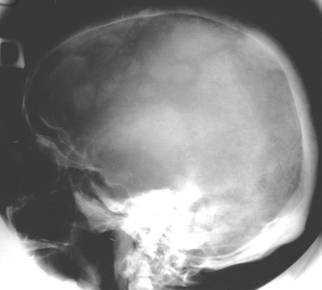

Fig. 99 – Osteosarcom osteogenetic fronto-parietal

Tumori maligne

a)   Osteosarcoamele,

Toate aceste tumori realizeaza aspecte radiologice similare cu cele deja descrise in capitolele precedente.